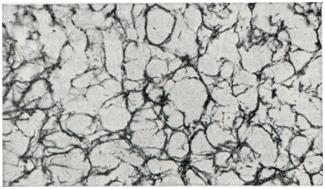

Микроскопически в ткани ангиоретикулемы обнаруживаются два компонента: 1) густая сеть сосудов капиллярного типа, имеющих вид каналов, щелей, более широких крововместилищ; стенки сосудов образованы одним слоем клеток эндотелия, 2) полигональные клетки со светлой цитоплазмой и небольшим ядром, содержащим нежную хроматиновую зернистость, располагающиеся между сосудами (рис. 1). Местами границы между клетками не видны или клетки формируют ретикулярную структуру. Часто цитоплазма содержит включения анизотропных липоидов («пенистые», «ксантомные» клетки).

Митозы обычно не встречаются. Иногда обнаруживаются тучные, плазмоцитоидные клетки. Могут наблюдаться очажки экстрамедуллярного кроветворения. В стенках сосудов с помощью импрегнационных методик выявляется характерное для ангиоретикулемы обилие ретикулиновых волокон, местами охватывающих и группы клеток межсосудистой ткани (рис. 2). Край опухоли образован петлями капилляров, переходящих в прилежащую мозговую ткань, и поэтому неровен. В опухоли или ее участках может преобладать какой-либо один из компонентов — сосудистый или клеточный.